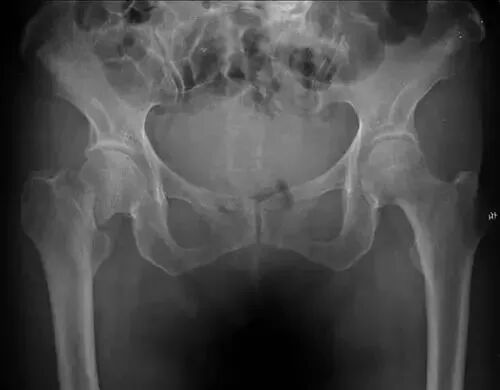

【普通放射图片】:

【影像表现】:X线骨盆正位示右侧股骨颈骨折,断端相互嵌入

【影像诊断】:右侧股骨颈嵌入型骨折。